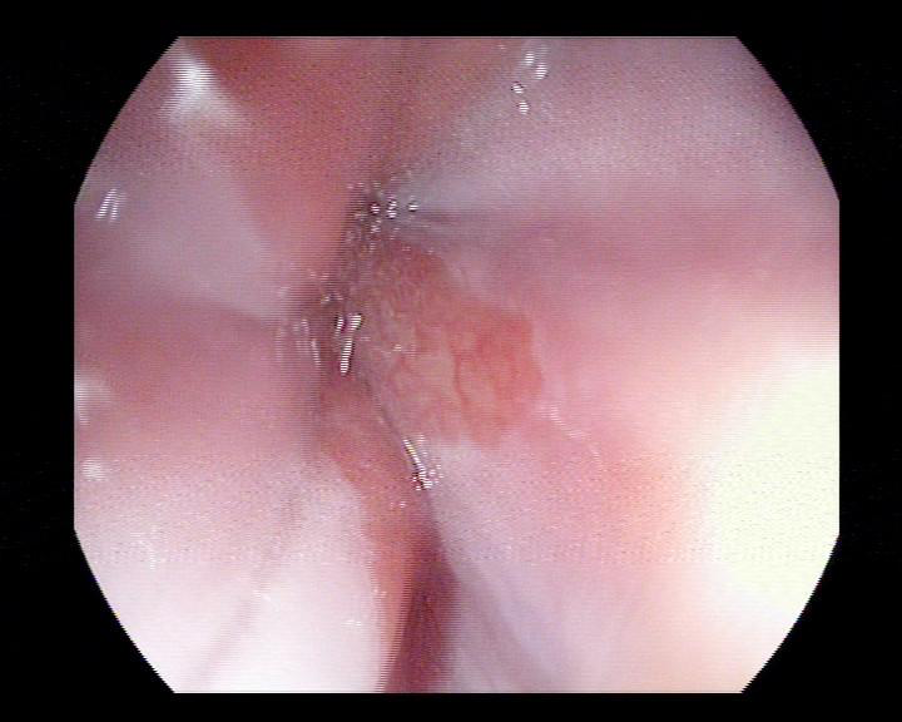

Nội soi đường tiêu hóa trên và làm sinh thiết tế bào giúp các Bác sĩ xác định được người bệnh có mắc Barrett thực quản hay không và mức độ tiến triển của bệnh thế nào để có những phương pháp điều trị hợp lý và chính xác. Phần lớn barret thực quản không có loạn sản, người bệnh nên nội soi định kì 6 - 12 tháng để theo dõi sự tiến triển của các tế bào trong thực quản.